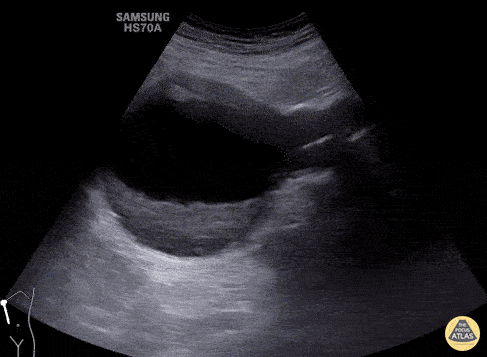

Aorta - Long Axis View of Large Abdominal Aortic Aneurysm

Long axis view of large abdominal aortic aneurysm containing intramural thrombus without evidence of the iliac arteries involvement. Image courtesy of Giovanni Battista Fonsi